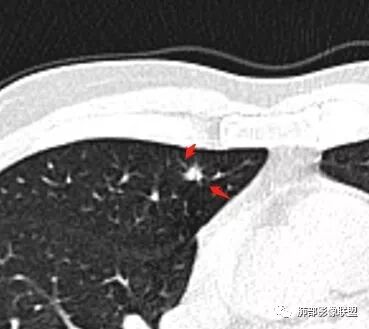

群内讨论

Ao..葉偲雨!👑:右肺中叶内侧段小结节,边缘毛刺,部分层面平直,第二次复查有凹陷,密度似乎比之前淡泊一点(肿瘤的生长周期一个月一般不会有太多变化),大小范围基本稳定,LU-Rads 4a类,炎性结节可能,建议3个月后复查或pet

密度遮盖了血管这是血管吧

这些?

这个?